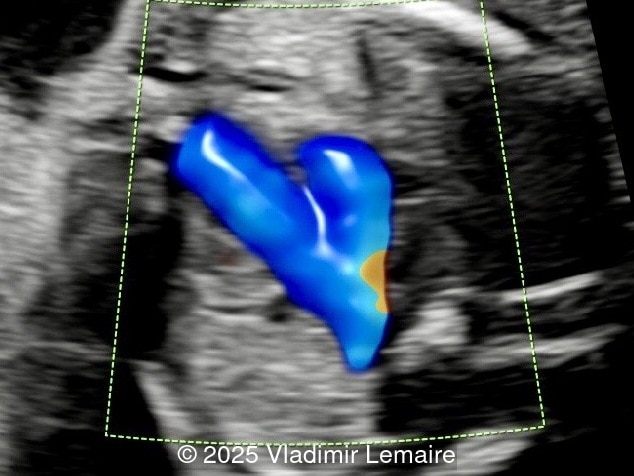

Image 1 Four-chamber view with color Doppler.

Four-chamber view with color Doppler.

Image 2 Four-chamber view with color Doppler.

Four-chamber view with color Doppler. Color Doppler confirms the absence of blood flow across the tricuspid valve in diastole.

Image 2 Four-chamber view with color Doppler. Color Doppler confirms the absence of blood flow across the tricuspid valve in diastole.

Color Doppler confirms the diagnosis on grayscale ultrasound, as it demonstrates the lack of blood flow across the tricuspid valve and a patent mitral valve. Due to increased blood flow across the mitral valve, aliasing is typically noted on color Doppler. Mitral valve regurgitation has been associated with a poor outcome. The right ventricular cavity is filled in late diastole from the left ventricle, through the ventricular septal defect. Left-to-right shunting across the ventricular septal defect can be seen on color Doppler. Color Doppler is helpful in the evaluation of flow across the great arteries. Flow across the pulmonary artery is generally antegrade. Pulmonary stenosis should be suspected when the vessel is diminutive in size rather than the demonstration of turbulent flow on color Doppler, which is typically absent in these cases.